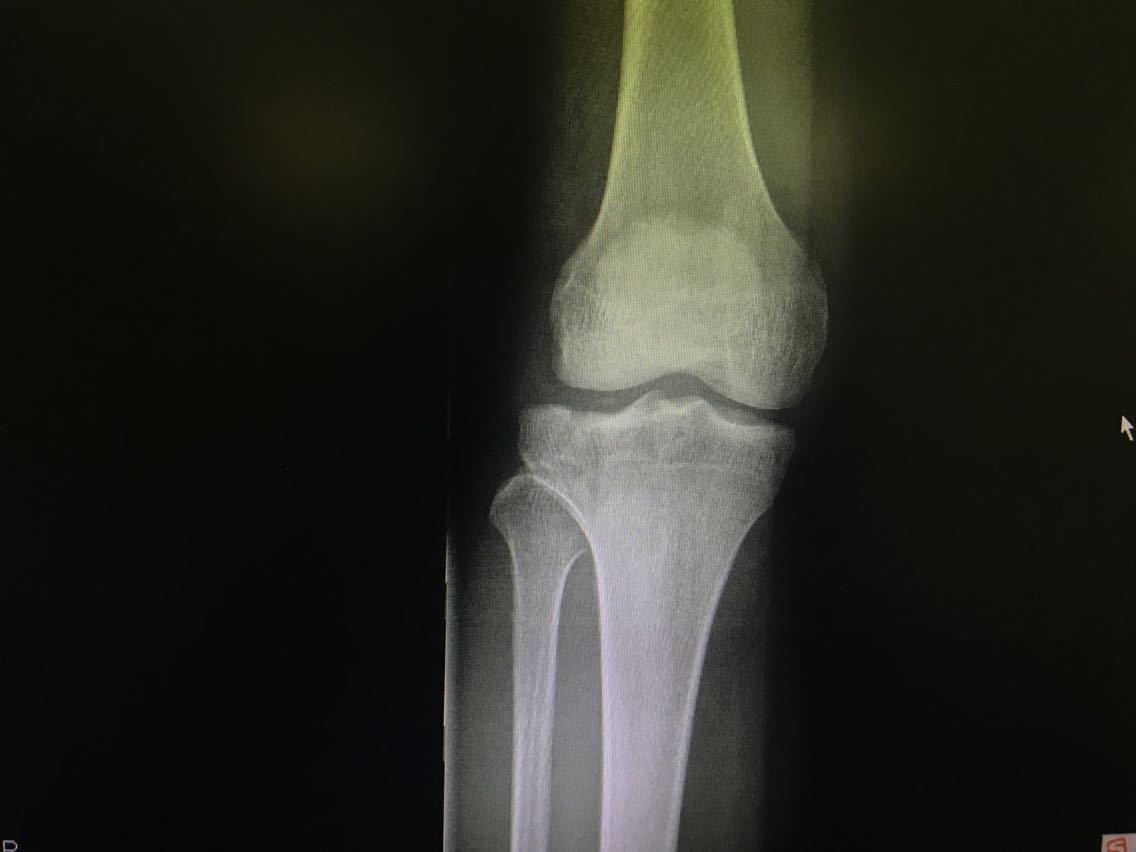

患者男性,26岁。 主诉:打篮球时受伤致右膝关节疼痛、功能障碍3天。 现病史:3天前患者打篮球时跳跃落地后以右足着地致右膝关节受伤,具体不详。伤后即感右膝关节剧痛,伴活动障碍,无意识障碍等不适。就诊于当地医院,给予对症处理后回家休息。3日来患者右膝关节疼痛无缓解,以屈曲时为甚。再次就诊于当地医院,行DR检查示:右胫骨平台骨折。患者为求进一步治疗,就诊于我院,急诊入我科。 既往史无特殊。

查体:右膝关节肿胀,下前方压痛,右膝关节呈强迫伸直位,被动屈曲时疼痛加重。 辅助检查: DR检查示:右胫骨平台骨折。

诊断:右胫骨平台骨折。 治疗:右胫骨平台骨折切开复位钢板螺钉内固定+右膝关节半月板修复+人工骨植骨。